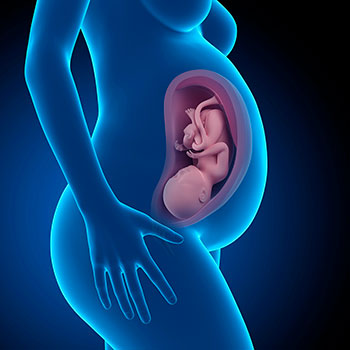

Estás de 39 semanas de gravidez e já falta muito pouco para o nascimento do bebé!

O bebé é suficientemente forte e o ambiente no qual, durante 9 meses, viveu protegido e cuidado, já começa a ser muito pequeno para ele.

Pesa entre 3 e 3,5 Kg e o seu comprimento é de 49-52 centímetros, em média.

Agora, o bebé faz cerca de 40 movimentos respiratórios por minuto. Os seus olhos, já grandes e bem formados, ainda vão demorar para sofisticar completamente as conexões neuronais que lhe permitem focar.

Os músculos do seu pescoço fortaleceram-se, pelo que agora é capaz de manter a sua cabeça separada do peito. Esta, por sua vez, pode ter cabelos, apenas algumas zonas com cabelo, ou cabelo nenhum.

Como já dissemos antes, o pequeno cada vez tem menos espaço à sua volta, embora todo o movimento, por pequeno que seja, o ajude a construir a sua força muscular e a melhorar a sua coordenação.

Idade do feto: 37 semanas.

O teu útero está completamente dilatado e a barriga alcançou o seu tamanho máximo.